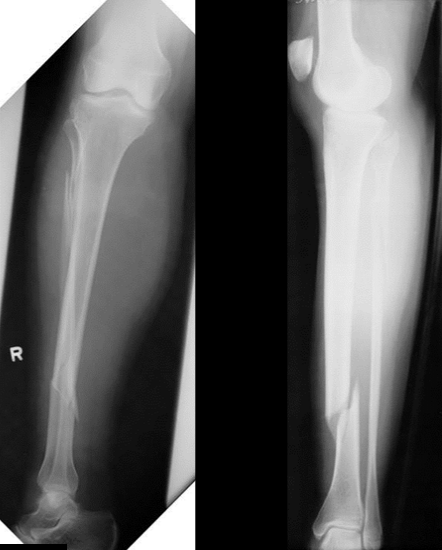

12

Q

What is the diagnosis?

What are some lesions associated with this injury?

A

Anterior shoulder dislocation

Associated with:

• Hill-Sach fracture (60%)

• Flap fracture (15%)

• Bankart lesion

• Labral tear

axillary nerve injury possible